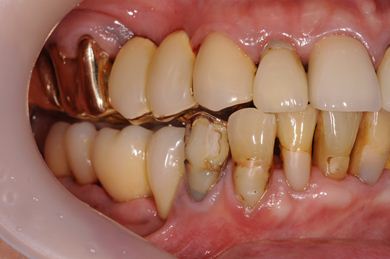

抜歯即日スピードインプラント治療+インプラント除去+セラミック治療

| 性別/年齢 | 女性 / 76歳 | ||||||||||||||||||||||||||||||||

| 主訴 | 20年前に入れたインプラントの周囲が腫れて気になっている。左下の一部治療後の歯が欠けている。 | ||||||||||||||||||||||||||||||||

| 治療内容 | インプラント5本(抜歯即日スピードインプラント)、ハイブリッドセラミック9本(セラミック用土台2本)、メタルボンドセラミック2本(メタルボンド用土台1本)、インプラント除去1本 | ||||||||||||||||||||||||||||||||

| 総治療費 | 2,514,645円 | ||||||||||||||||||||||||||||||||

| 治療期間 | 1年11ヶ月 |